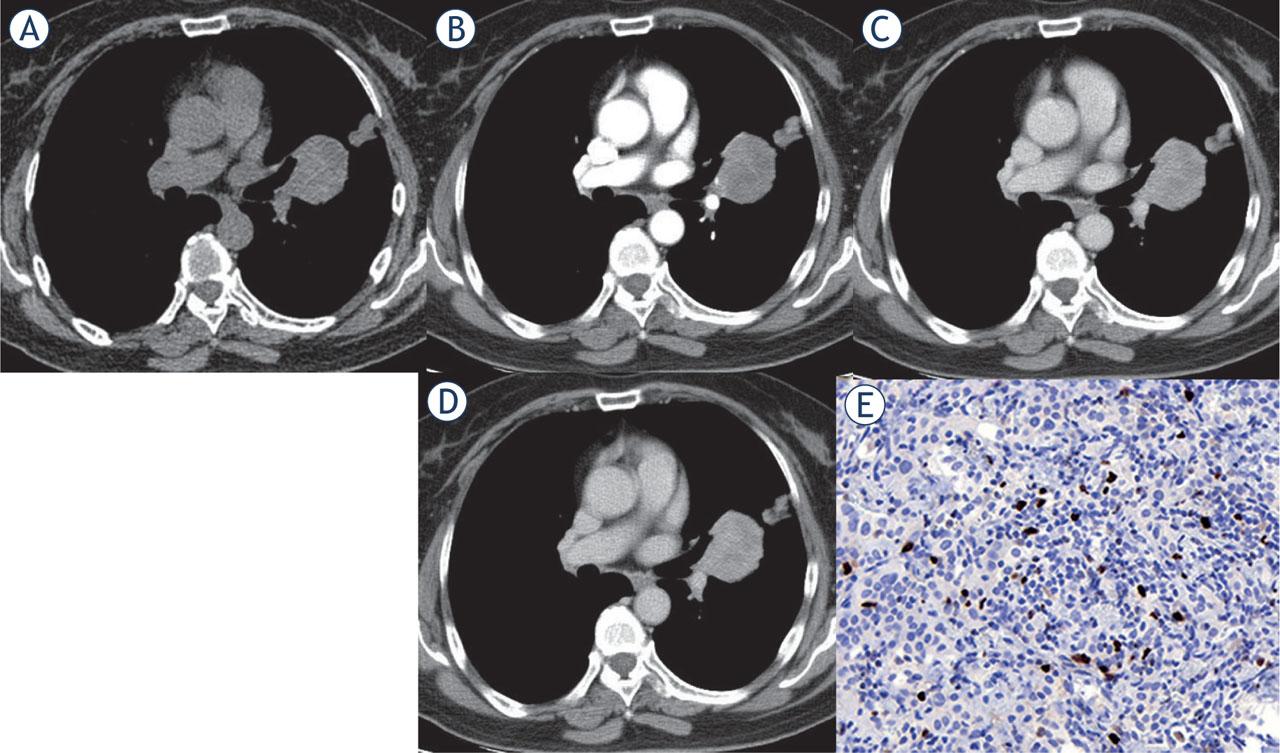

Multi-phase contrast-enhanced CT of central PSP with higher Ki-67 index. Axial unenhanced CT image revealed a roundish isodense lesion in the left perihilar region with a CT density of 49 Hu (A). After administration of contrast medium, the lesion showed inhomogeneous enhancement with the enlarged left inferior pulmonary artery and overlying vessel sign (B). The lesions showed progressive and continuous enhancement in the arterial phase (75 Hu) (B), venous phase (96 Hu) (C), and delayed phase (110 Hu) (D). Immunohistochemical staining showed the Ki-67 reactive tumor cells accounted for about 10% (× 400) (E).